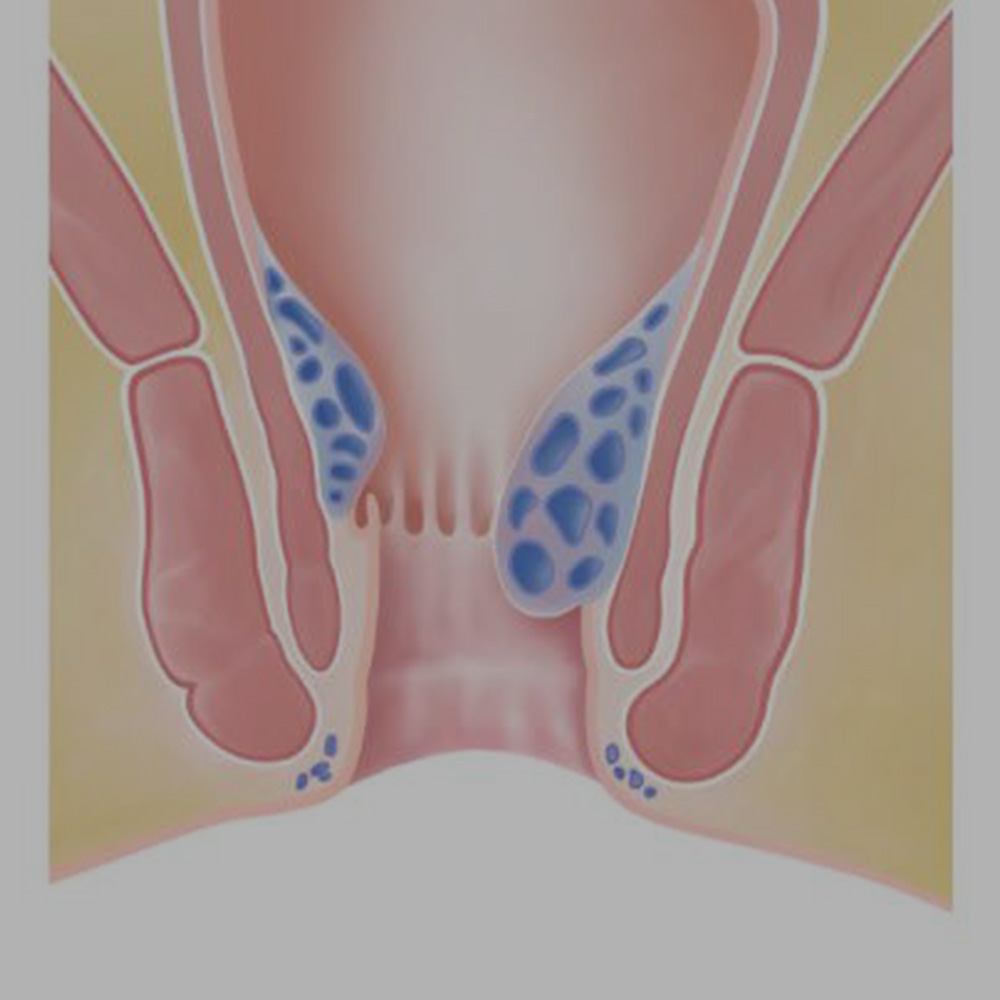

Hemoroid "Basur"